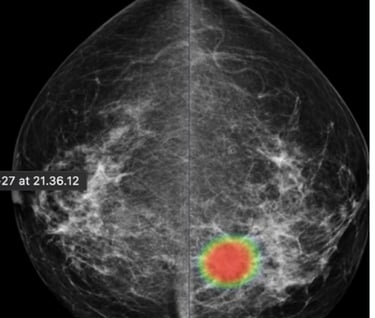

DAM - Breast Solution

To help radiologists improve the predictive accuracy of screening mammography, we present a deep learning method that can detect breast cancer on screening mammograms using a "end-to-end" training technique that efficiently leverages training datasets with either full clinical annotation or merely the cancer status (label) of the entire image. Our training data include biopsy confirmed types of benign or malignant tumors.

Breast cancer detection

Tumor type classification

Breast cancer metastases localization